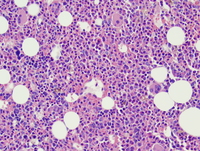

Bone marrow aspirate

Variable degrees of dysplasia are seen in erythropoiesis, granulopoiesis, and megakaryocytes.

RAEB-1 is defined by 5-9% blasts in the bone marrow. RAEB-2 is defined by 10-19% in the bone marrow. The presence of Auer rods in blasts qualifies as RAEB-2 irrespective of the blast percentage.